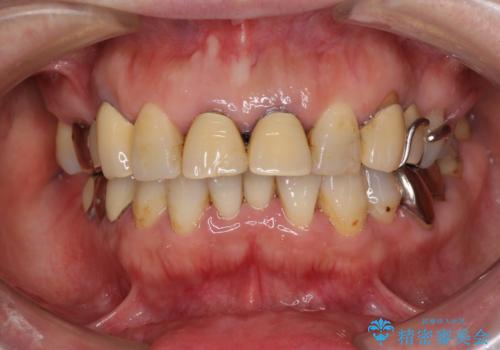

神経が露出しないよう慎重に行った結果、神経を保存することができました。処置後に多少の痛みが生じましたが、その後は良好な状態が続いています。

色、形ともに、自然な仕上がりとなり、患者様には大変満足していただきました。